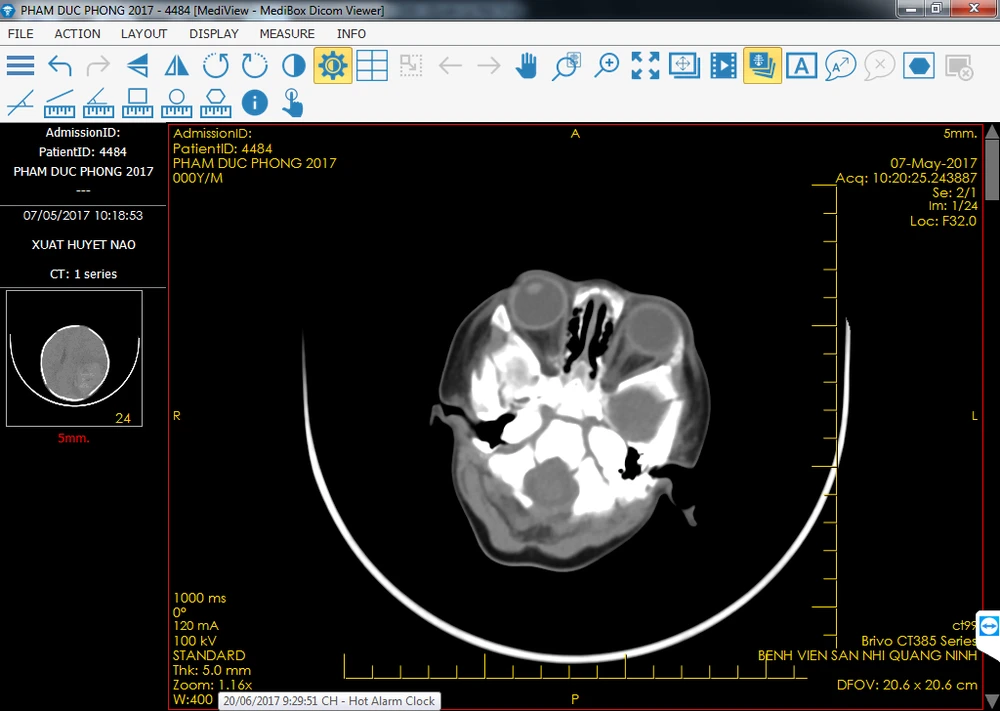

Kết quả xét nghiệm và chẩn đoán hình ảnh cho thấy bé bị thiếu máu nặng, rối loạn đông máu; hình ảnh máu bán cầu não trái có xuất huyết não bên trái, phù não… Bé được thở máy, truyền máu, tiêm vitamin K, kiểm soát áp lực nội sọ.

Qua hội chẩn chuyên khoa, các bác sĩ chẩn đoán trẻ bị: Xuất huyết trong não lan rộng, tại nhiều nơi và chỉ định phẫu thuật lấy máu tụ trong sọ, ngoài màng cứng, dưới màng cứng cho bé.